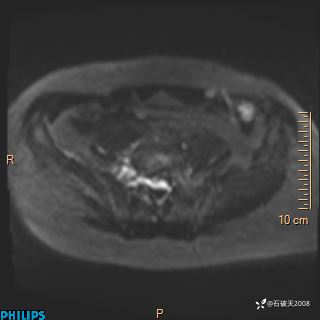

2023年3月份MRI影像

ADC

现病史:7个月前患者因骶尾部占位就诊于北京大学人民医院,MRI示:骶骨右侧及右骶前占位,考虑骨巨细胞瘤可能,动脉瘤样骨囊肿可能,神经源性肿瘤待排。行手术治疗,术后病理回示:XXXXX。术后给予对症治疗,具体不详,恢复良好。近几个月反复出现发热,伴骶尾部不适,多次住院给予对症治疗,2天前患者无明显诱因再次发热伴骶尾部不适,无大小便失禁,为求进一步治疗,遂门诊来我院,在门诊初步检查后,以“骶尾部肿物”为诊断收入我科。入院来患者神志清,精神一般,饮食睡眠可,大小便无明显异常,体重无下降。